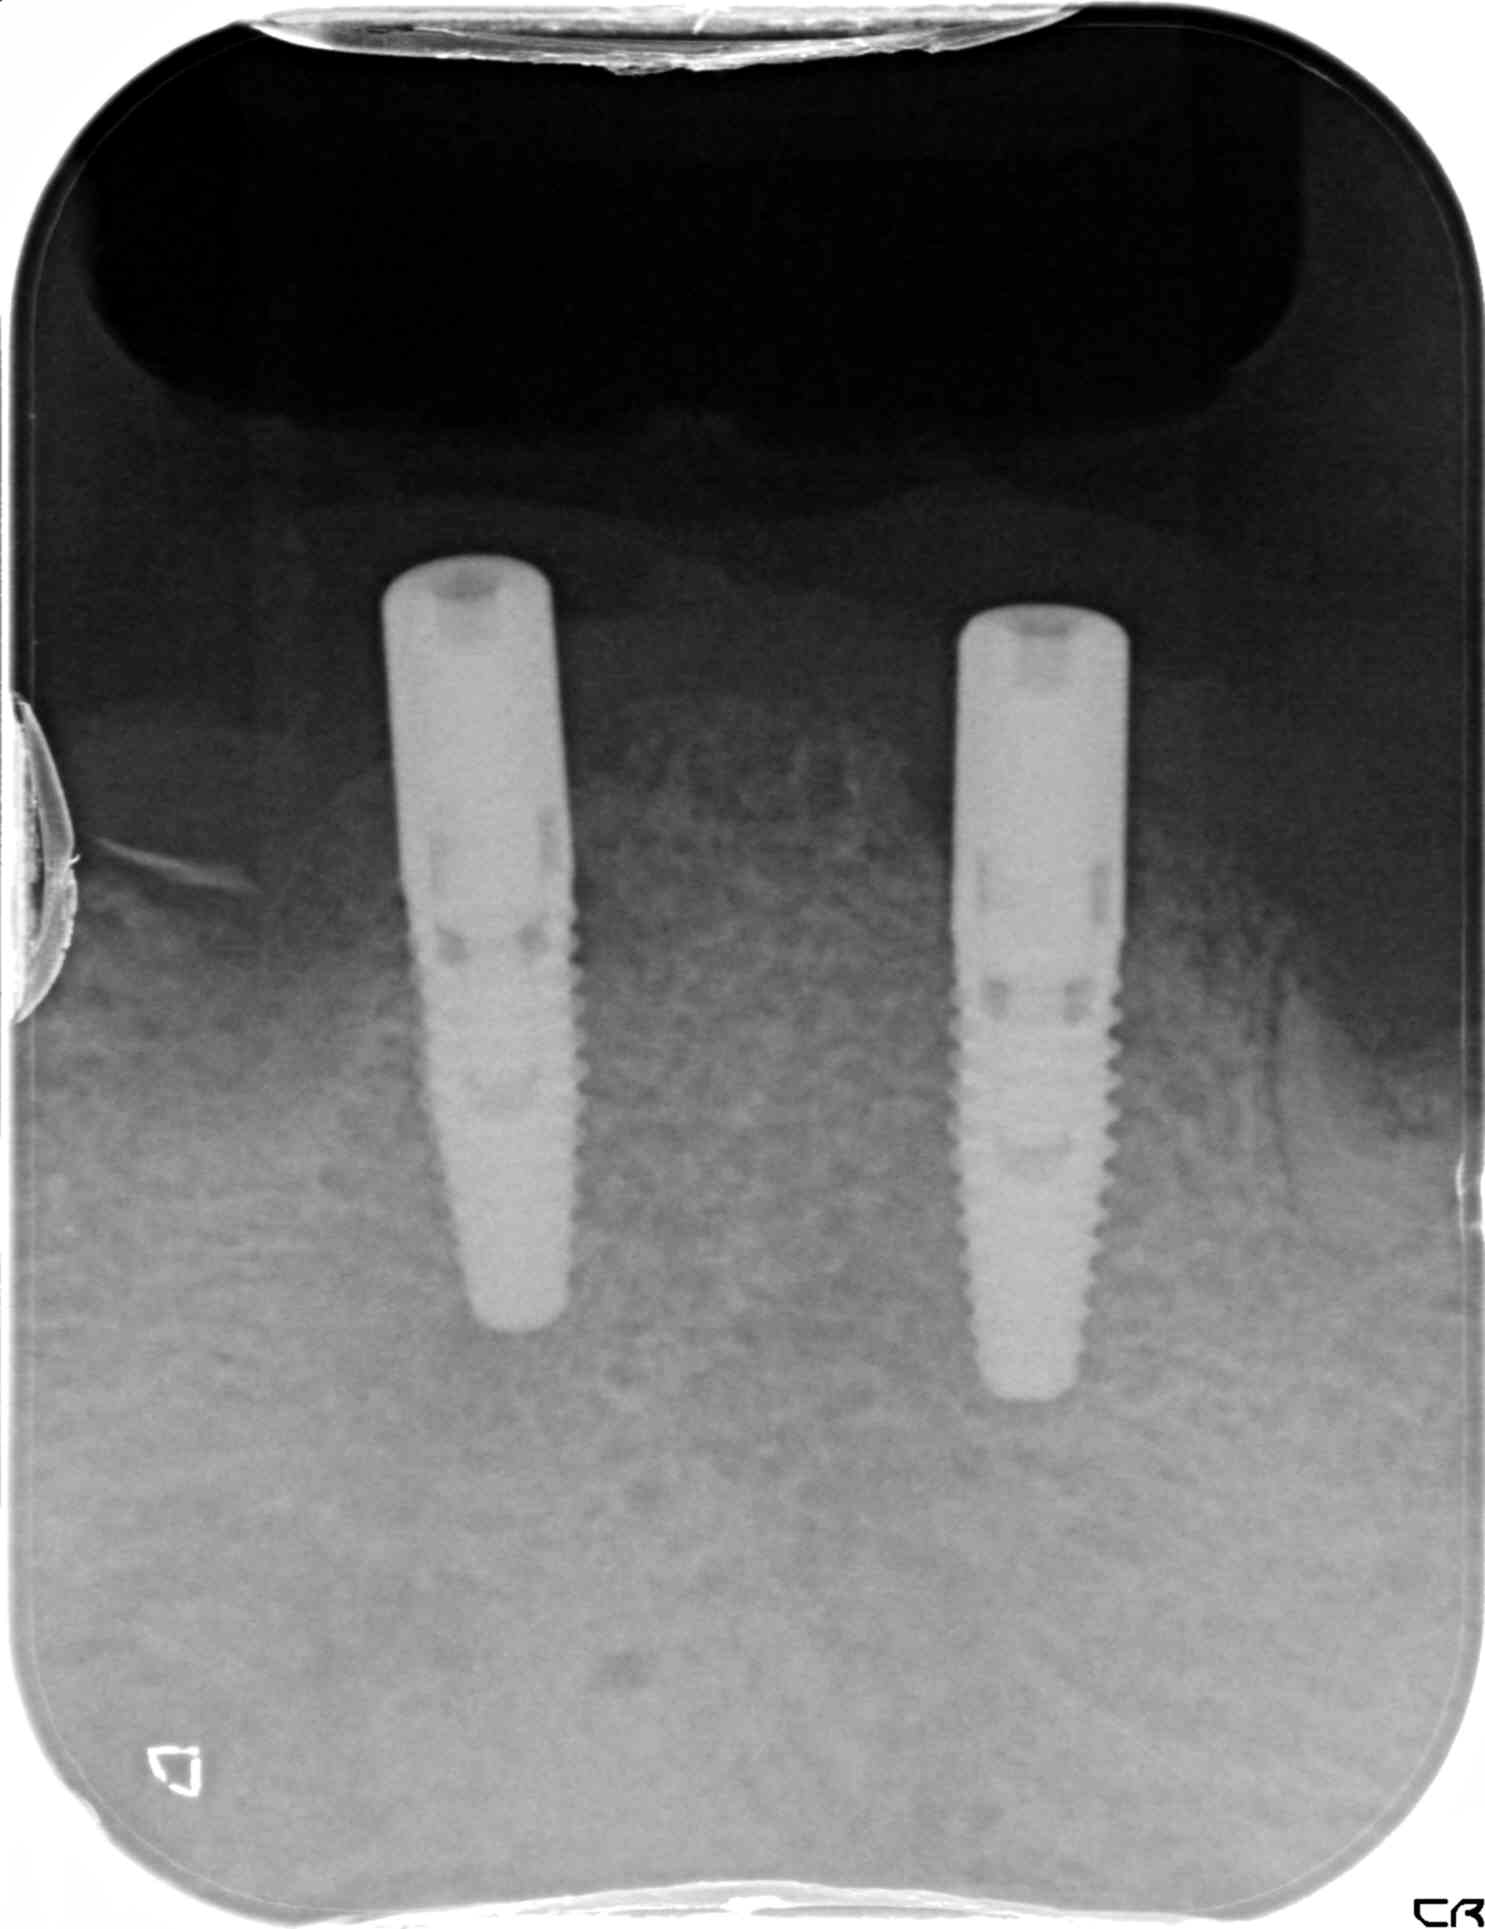

その後、下顎に2本のインプラントを埋入し、3か月後にはインプラントにロケーターアバットメントを装着しました。これは、義歯を安定的に支えるためのパーツで、インプラントに装着された金色のパーツ(赤色矢印)が、入れ歯の安定性を高める役割を果たします。

インプラントを介して咀嚼力が直接下顎の骨(歯槽骨)に伝達されるため、骨の吸収(廃用性萎縮)の予防にも効果があります。